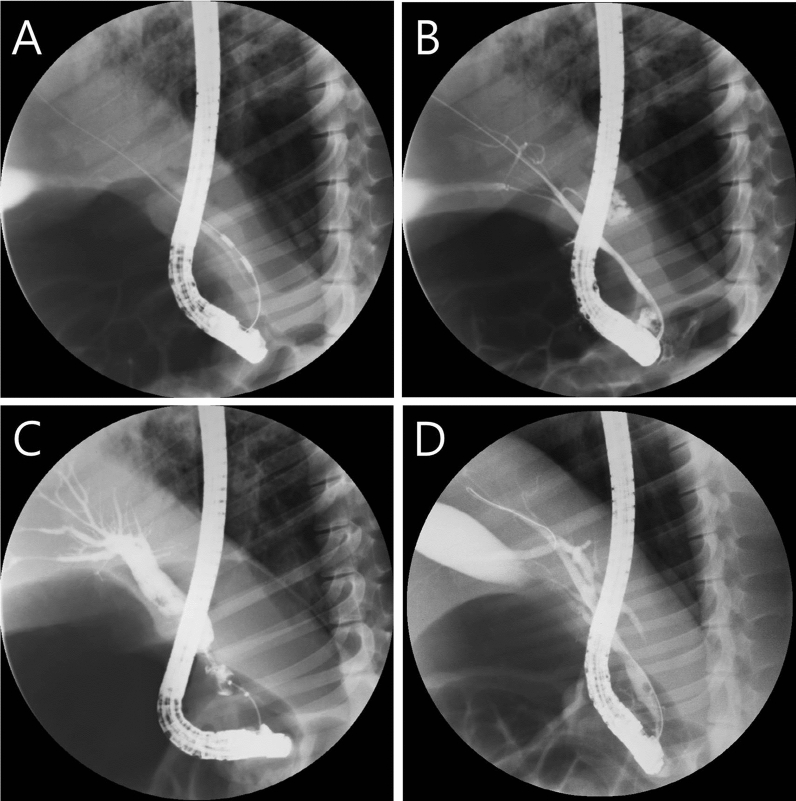

We planned to euthanize one animal every five days after performing endobiliary RFA on five animals and perform sequential histological examinations. Before the histological examination, gross examination to evaluate CBD rupture, perforation, bleeding and BBS degree was performed. Based on the results of the first experimental trial, we had to prevent BBS-induced biliary obstruction and secondary cholangitis. Therefore, a plastic stent (single pigtail-type, 5 Fr, 7 cm, with flap: Zimmon® Pancreatic Stent, Cook Medical, Bloomington, IN, USA) was placed for biliary drainage after RFA application.

The remaining four animals were euthanized 5, 10, 15, and 20 days after the procedure. On macroscopic examination, the inserted plastic stent was visible in only two out of four animals (Fig. 5A). Perforation or other adverse events were not observed in any of the four animals. The stricture initially was mild in the RFA application area in the distal CBD of the first animal, and the stricture and upstream CBD dilation were clearly observed in the second animal (Fig. 5B). Those areas became thicker and more prominent over time in the third and fourth animals. On microscopic examination (Fig. 6), the CBD of the first animal demonstrated extensive abscess formation at the APC application area, but no fibrosis was found. In the CBD of the second animal, the majority of the wall was replaced with an abscess at the APC application area, but fibrosis had begun, as evidenced by Masson’s trichrome stain. In the third and fourth animals, the abscess formation greatly improved, and the thickened wall was nearly and completely replaced by fibrosis.

Results of the third in-vivo study step

Based on the previous steps and the objective to prevent stent migration, biliary plastic stents were replaced with double-pigtail-type (5Fr, 9 cm: Zimmon® Biliary Stent, Cook Medical) and inserted after RFA in 12 animals. The proximal ends of the stents did not return to their original shape, indicating that they had an anchoring effect within the CBD. During the follow-up period, one out of 12 animals died unexpectedly (8.3%) 13 days after the RFA procedure. The autopsy revealed that there was no perforation or necrosis. In the 11 surviving animals, blood analyses showed mild cholangitis during the two weeks after RFA but no cholangitis four weeks after RFA (Table 2). ERC was obtained four weeks after the procedure to confirm the degree of BBS. Stent migration occurred in only one out of 11 animals (9.1%). The median length of the stricture area was 27.0 mm (17.4–30.9 mm), and the median diameter of the upstream dilation was 14.4 mm (11.1–20.7 mm) (Table 3). On histopathologic examination (Fig. 7), the average fibrotic wall thickness of the BBS was 1107.9 µm (763.1–1864.6 µm).